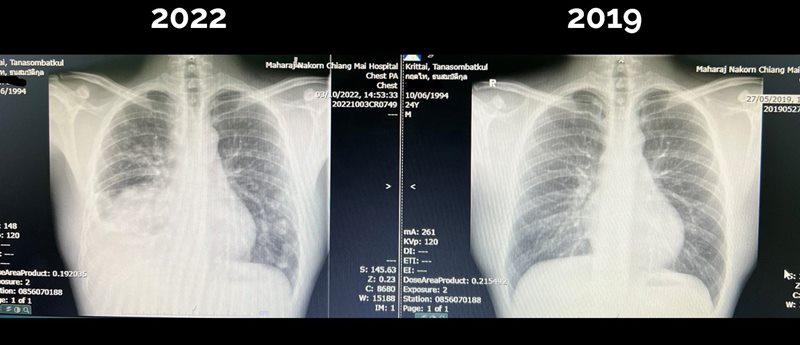

เป็นเรื่องราวที่ถูกแชร์กันในโลกออนไลน์ขณะนี้ สำหรับโพสต์จากเพจ "สู้ดิวะ" ของ คุณหมอกฤตไท ธนสมบัติกุล แพทย์หนุ่มอนาคตไกล วัย 28 ปี

ที่เพิ่งพบว่าตัวเองป่วยเป็นมะเร็งปอดระยะสุดท้าย

ภาพจาก เฟซบุ๊ก Krittai Tanasombatkul